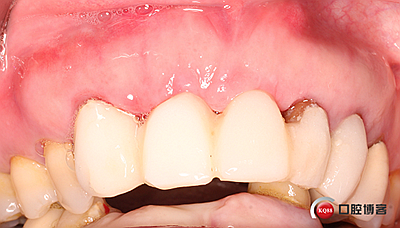

術(shù)后兩個(gè)月。

術(shù)后4個(gè)月,三顆牙變?yōu)閮深w牙齦乳頭改造是難點(diǎn)。